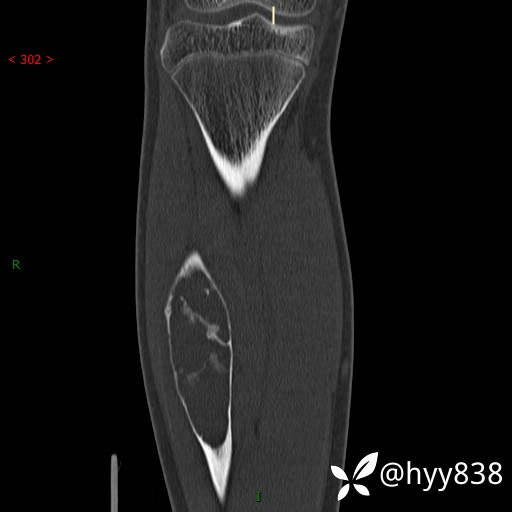

CT MPR COR